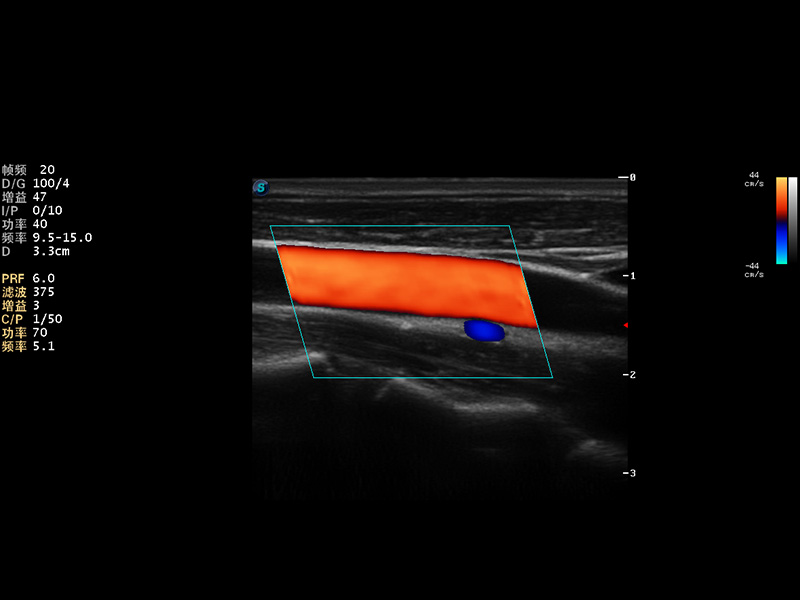

S9便携式彩色多普勒超声诊断仪是百老汇电子游戏官网研发的高端便携彩超设备,外观设计新颖、产品性能卓越。S9在便携超声领域采用了突破传统的触摸屏交互设计,并以先进的软件硬件技术和设计理念,为您带来清晰的图像质量、稳定的工作性能和便捷的操作体验。

AutoC智能血流追踪